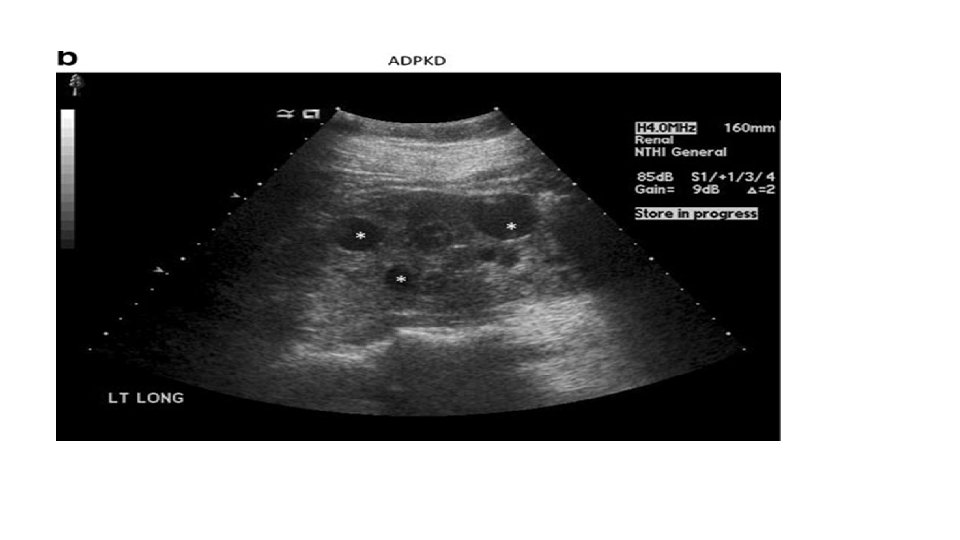

Physical Examination q. The following should be evaluated to assess for potential causes of the hypertension: • Body mass index may lead to an evaluation for metabolic syndrome. • Tachycardia may indicate hyperthyroidism, pheochromocytoma, and neuroblastoma. • Growth retardation may suggest chronic renal failure. • Café au lait spots may point to neurofibromatosis. • An abdominal mass may lead to an evaluation for Wilms tumor and polycystic kidney disease.

Basic Investigations • CBC : R/O anemia, consistent with chronic renal disease. • BUN, creatinine, electrolytes, urinalysis and urine culture: R/O renal disease and chronic pyelonephritis. • Renal U/S : congenital anomaly, renal size. • Renal Doppler US. • Thyroid Function Test. • Echocardiogram(LVH).